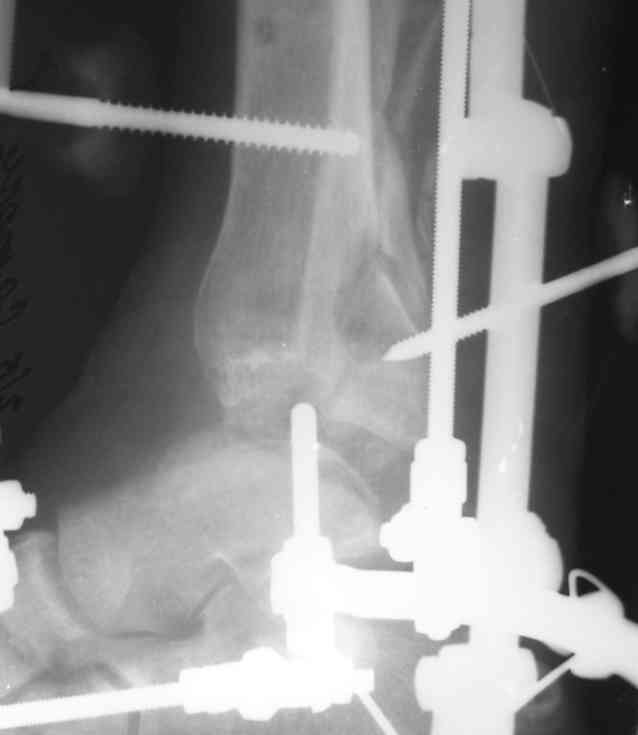

Задний край достаточно большой и поставить его на место следовало бы. Подтянуть задний край можно тонким стержнем Шанца диаметром 3-3,5-4 мм с резьбой на хвосте, вкрученным в задний край спереди через канал большего диаметра. Вариант этим же стержнем, но из задне-латерального прокола. Отправляю пример.

После сопастовления заднего края постепенная компрессия зоны перелома.